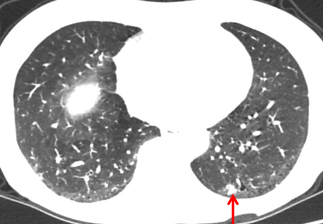

2014-10-08:

肺窗: 多发结节,最大5.99*9.65mm

肺部结节较前明显增大,肺窗17.23*19.06mm

肺部结节,肺窗17.23*19.06mm

肺窗:13.97*16.73mm